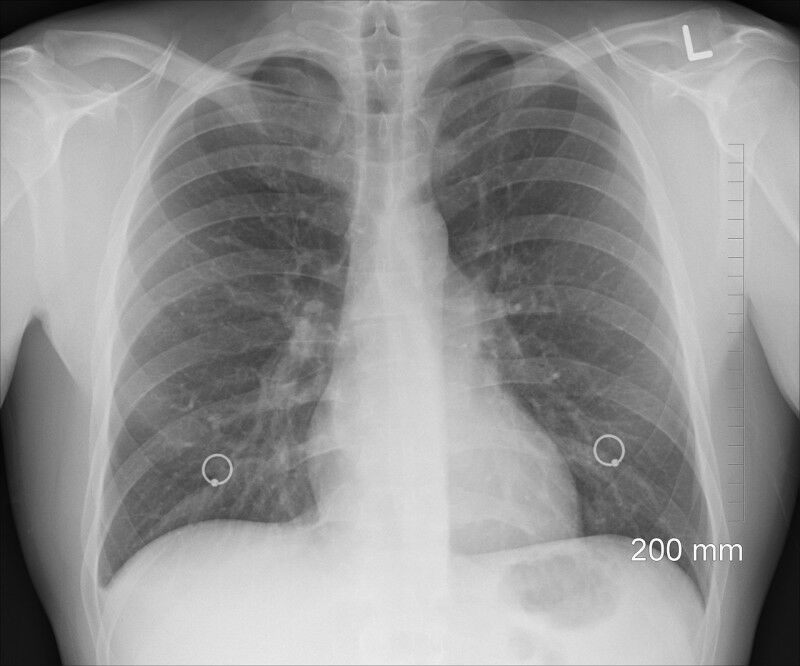

This approach reduces the volume of lung tissue that needs to be removed by up to 4 times. (Image: Pixabay CC0) - A new surgical approach for people who are detected with early-stage lung cancer has been shown to be as effective and safe as the surgery commonly used for these patients. The merits of this approach, which preserves more of the lung, were recently demonstrated in the New England Journal of Medicine by a North American research team that includes Massimo Conti , a professor in the Faculty of Medicine at Laval University, a thoracic surgeon at the Institut universitaire de cardiologie et de pneumologie de Québec (IUCPQ), and a researcher at the IUCPQ-Université Laval Research Centre The human lungs are subdivided into 5 lobes. When a non-metastatic tumor is found, the current standard is to perform a resection of the affected lobe. "Advances in medical imaging and the implementation of screening programs now allow for earlier detection of lung tumors. These advances call into question the need to remove an entire lobe, but partial lobar resection had to be proven to be effective and safe for patients," says Massimo Conti. To do this, the researchers recruited 697 people who had a tumor less than 2 cm in diameter in one lung, with no lymph node metastasis.